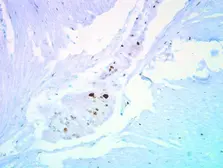

Images